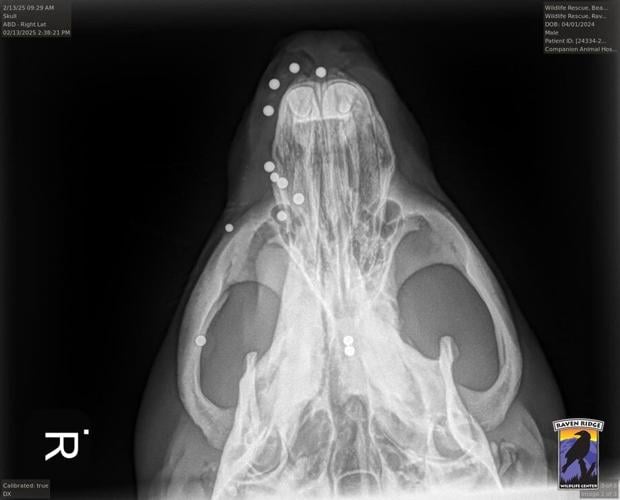

When the beaver was X-rayed, the staff were surprised to find 14 bb-sized pellets lodged inside the beaver’s head. Young said pellets were found in its sinuses, causing severe infection. Another pellet had blinded the beaver in its left eye.

The center was advised by veterinarians not to remove the pellets as it could be too traumatic to survive. Some might be pushed out naturally by the beaver’s body, while others are likely to remain embedded in the animal.